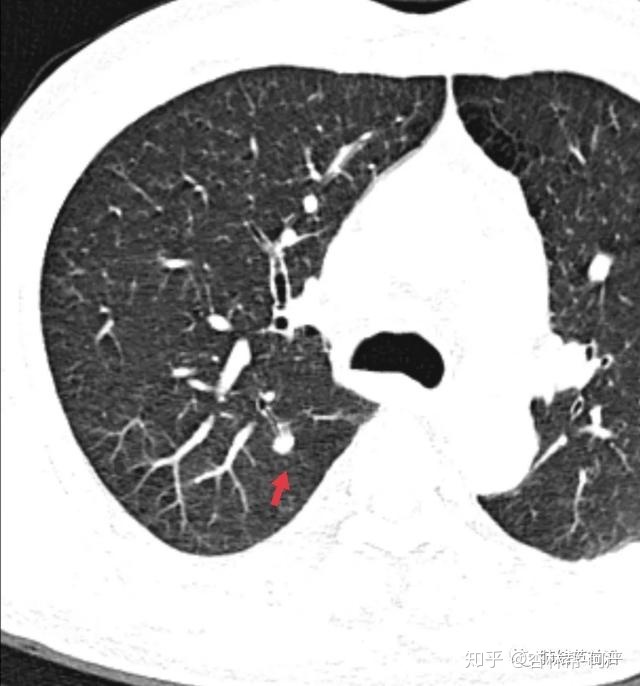

结节1:7mm实性结节,边界光滑,CT图像大概率为良性结节。

结节1:CT值为197,诊断为纤维灶结节。